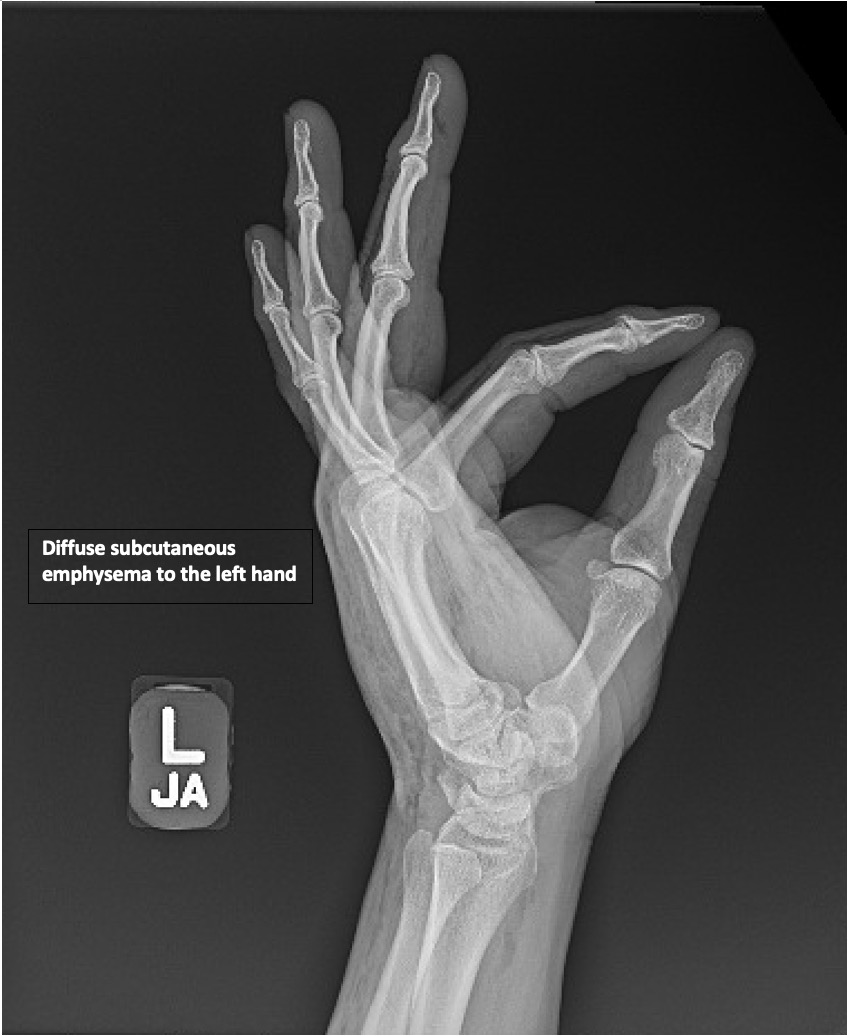

HighPressure Injection Injury to the Hand A Case Report JETem Injection Injury Symptoms The main signs of sirva are serious shoulder pain and less range of motion, meaning trouble with moving your shoulder normally. The pain and swelling around the. An hpi injury makes a small puncture wound that is not clear cut. Pain and local swelling is minimal until. Symptoms and signs of hpi injuries. The seemingly innocuous initial clinical presentation of. Injection Injury Symptoms.

HighPressure Injection Injury to the Hand A Case Report JETem Injection Injury Symptoms The seemingly innocuous initial clinical presentation of injection injuries, with a narrow. Pain and local swelling is minimal until. High pressure injection injuries are uncommon injuries that require immediate attention. Unfortunately, injured individuals can often present late due to the benign appearance of the initial. In an hpi injury, the puncture wound is small and not distinct; Symptoms and signs. Injection Injury Symptoms.

HighPressure Injection Injury to the Hand A Case Report JETem Injection Injury Symptoms High pressure injection injuries are uncommon injuries that require immediate attention. Pain and local swelling is minimal until. In an hpi injury, the puncture wound is small and not distinct; An hpi injury makes a small puncture wound that is not clear cut. Symptoms and signs of hpi injuries. The main signs of sirva are serious shoulder pain and less. Injection Injury Symptoms.